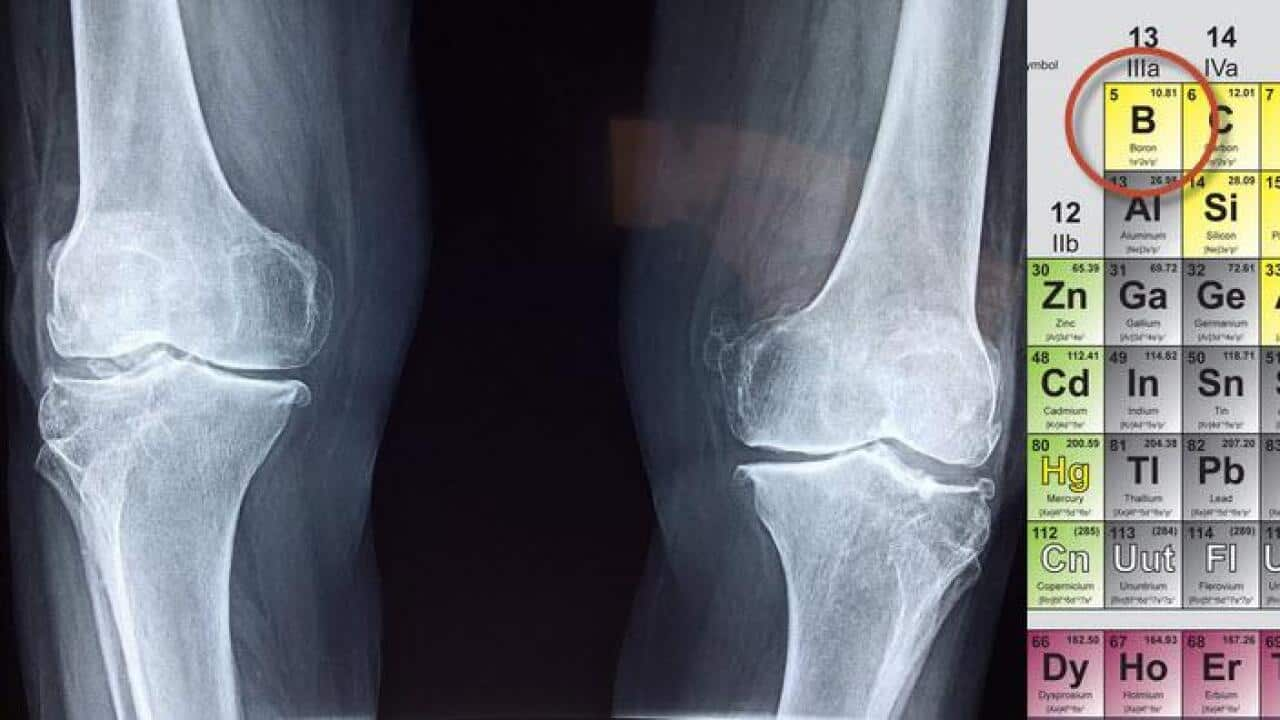

Boron has an important role in the treatment of osteoporosis Source: pixabaj public domain